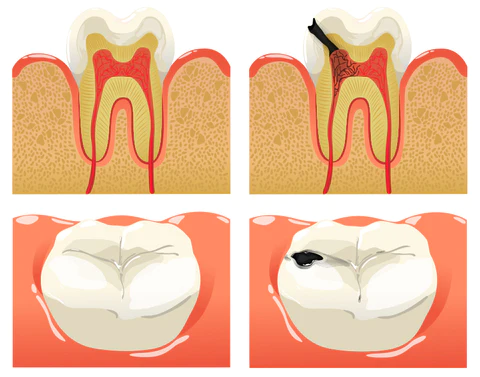

Dental caries develop when germs damage tooth enamel and gradually penetrate into the dentin and even the pulp. This can result in bad breath, toothaches, weakened teeth, and potential tooth loss. The presence of caries often triggers a chain reaction, causing healthy teeth to be affected as germs spread to adjacent teeth.

Prevent Cavities

FURZERO™ Herbal Brightening Oral Repair Foam can help you kill bacteria that penetrate deep into the alveolar and root canal, stimulate the restorative formation of dentin, and help repair tooth decay. For severely necrotic cavities, it can stimulate the gums to produce new tooth germs and promote the growth of new teeth.